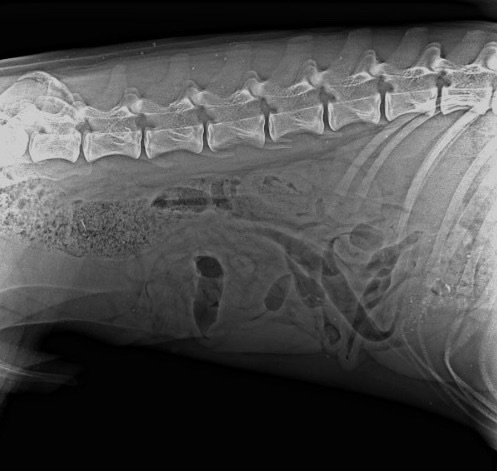

Осталось разобраться с самым главным,- у Кая полиtравма, переLом лучшевой кости, РПКС справа, выvих латеральный надколенника справа. Стоимость двух опер (оsтеосинтез) 104 300 рублей (2 опер). На одну опер мы собрали, завтра утром Кай будет проопер., а на вторую опер денег ни копейки НЕТ…